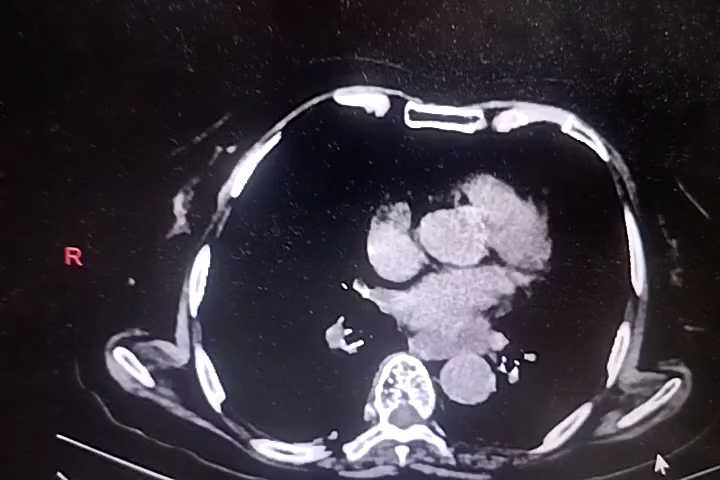

胸部+全腹部CT结果回报:双肺支气管炎,通气不良,双肺底多发索条,考虑1、膨胀不良2、慢性炎症,左肺下叶钙化灶,主动脉钙化,食管裂孔疝,纵隔多发淋巴结,肝门区钙化灶,胆囊密度低密度增高,考虑胆汁淤积,右肾囊肿?建议强化,双肾盂、输尿管扩张,膀胱过度充盈,考虑尿潴留,结合临床,直肠积粪密切观察病情变化。

心脏超声:主动脉瓣退行性病变并少量反流,二尖瓣、三尖瓣少量反流,左心功能减低。